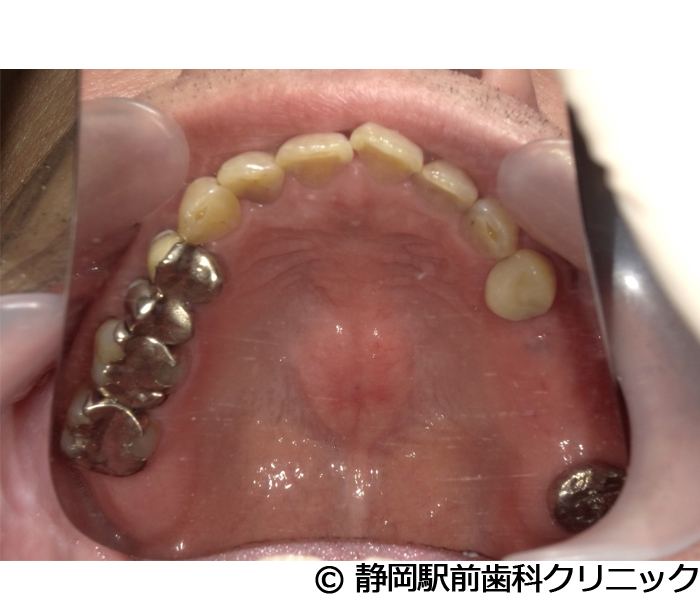

【症例5】全顎的インプラントとセラミックによる審美補綴

- 治療前

- 治療後

- 治療名

- 全顎的インプラントとセラミックによる審美補綴

- 費用

- 1,800,000円(税込)

- 期間

- 1年6ヵ月

治療内容

患者様の症状

全体的に歯がないため、噛めない。インプラント治療希望。

治療方法

全体的に残根は抜歯を行い、術前にCTを撮影し緻密に治療計画を立てた。インプラント埋入はブロックごとに行い、噛み合わせの調整を重ねた後、人工歯を被せて咬合と審美の回復を行いました。

治療結果

しっかり奥歯で食べ物を噛み切ることができるようになり、何でも食べることができるようになったと喜んでいただくことができました。口元を気にせずに笑うこともできるようになり、見た目もキレイになったとご満足いただけました。

※治療結果は個人差があります。

治療を行う上での注意点(リスク・副作用)

術後は、出血、腫れ、痛みなどが出る可能性があります。